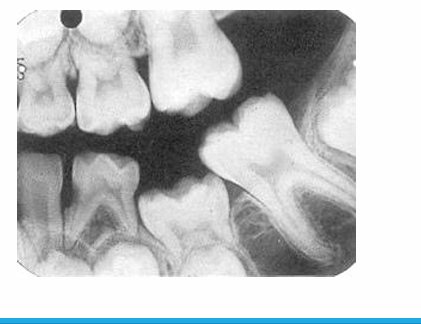

panoramic radiograph

-evaluate growth and development

-take pans in children if unerupted teeth exist that should be erupted

-some practitioners say every 3 yrs starting at age 6

-look at overall development of child

-23, 24, 25, 26, 1st year molars present = good time to take pan

-anomaly: ankylosis

-peg lateral

-supernumerary primary lateral

-count the teeth

-fusion

-supernumerary tooth

-missing lateral

-concrescence: cementum fuses together

-unfavorable resorption pattern of roots

-retained primary root tips

-common in kids with high caries → don’t get tx and teeth just crumble